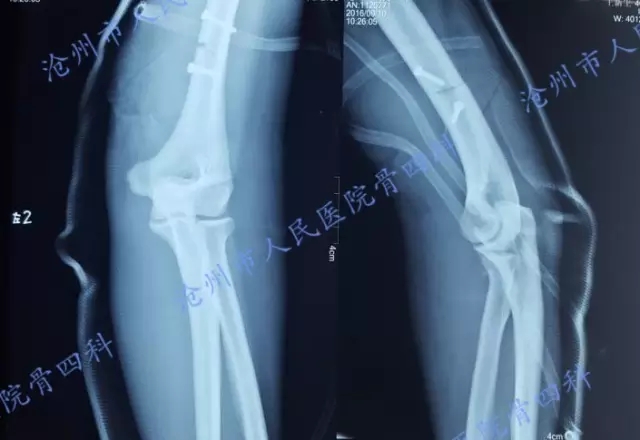

小结:热压伤后保肢艰难,术后易出现瘢痕增生,痛觉过敏,肢体功能严重受损,甚至造成关节挛缩,影响患肢功能。例如来自中华手外科网的一张照片所示,肘关节及腕关节均受到不同程度的影响。